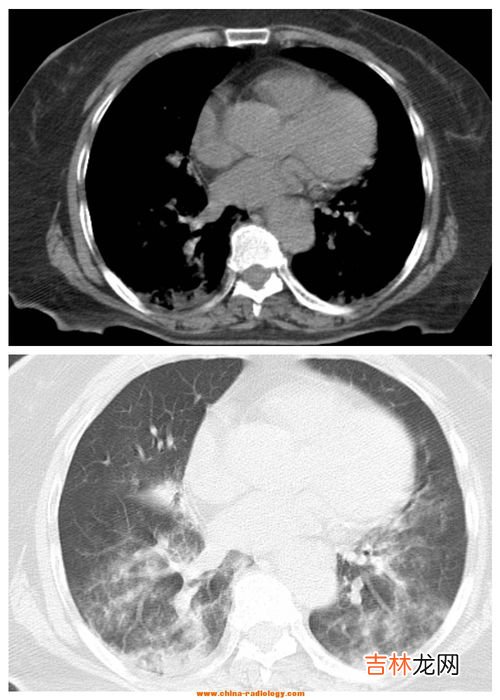

文章插图

3、什么是间质性肺炎间质性肺病(Interstitial lung Disease,简称ILD) 是以弥漫性肺实质、肺泡炎和间质纤维化为病理基本改变,以活动性呼吸困难、X 线胸片示弥漫阴影、限制性通气障碍、弥散功能(DLCO)降低和低氧血症为临床表现的不同类疾病群构成的临床病理实体的总称 。ILD 通常不是恶性的 , 也不是由已知的感染性致病源所引起的 。继发感染时可有黏液浓痰,伴明显消瘦、乏力、厌食、四肢关节痛等全身症状,急性期可伴有发热 。

间质性肺炎是肺的间质组织发生炎症炎症主要侵犯支气管壁肺泡壁,特别是支气管周围血管周围小叶间和肺泡间隔的结缔组织而且多呈坏死性病变 。间质性肺炎大多由于病毒所致主要为腺病毒呼吸道合胞病毒流感病毒副流感病毒麻疹病毒等其中以腺病毒和流感病毒引起的间质性肺炎较多见也较严重常形成坏死性支气管炎及支气管肺炎病程迁延易演变为慢性肺炎 。肺炎支原体也能引起间质性肺炎支原体经呼吸道侵入后主要侵犯细支气管和支气管周围组织由于无破坏性病变故能完全恢复 。